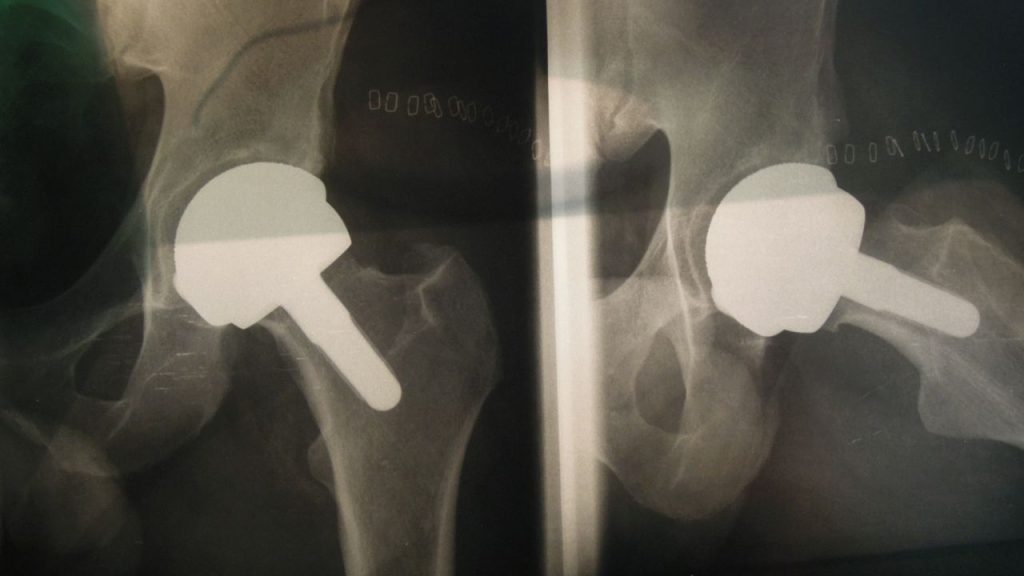

magnani-lastra-2

magnani-lastra-4

magnani-lastra-3

magnani-lastra-1

magnani-lastra-5

Chirurgia Protesica Mini-Invasiva

• Protesi di anca (accesso mini-invasivo)

• Protesi di ginocchio (mono/bi/tricompartimentale)

• Protesi di spalla (anatomiche e inverse)

• Protesi di caviglia (mini-invasive, con carico precoce)